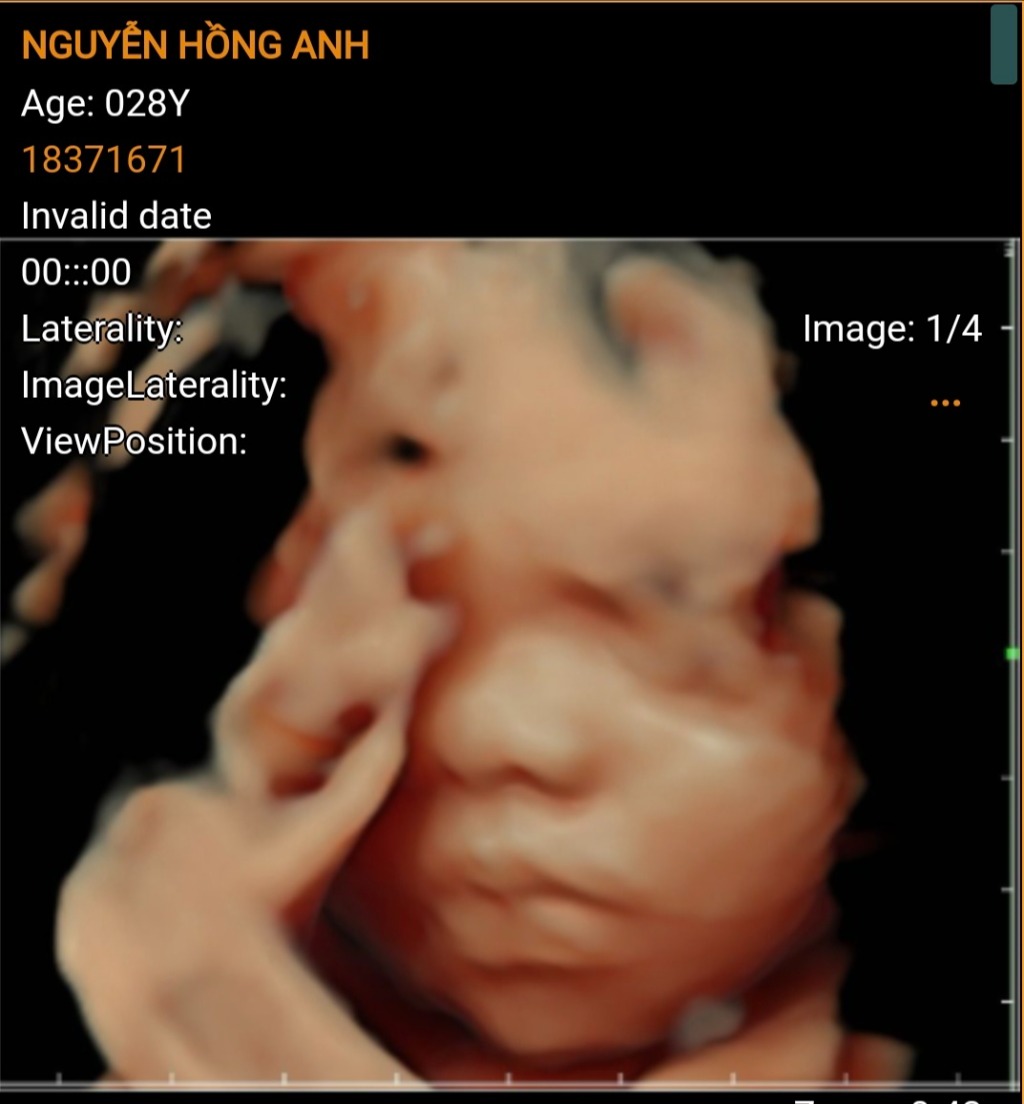

Nguyễn Hồng Anh